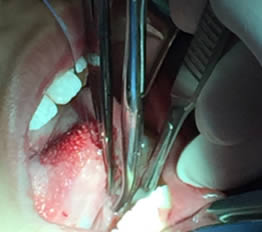

• Se colocó anestesia tópica y se infiltró localmente (lidocaína con epinefrina de 1: 100 000 al 2 %) a cada lado del frenillo lingual bloqueando nervio lingual bilateralmente. (Figuras 1 y 2).

Figura 1. Anestesia Local a cada lado del frenillo.

Figura 2. Anestesia Local del nervio lingual bilateralmente

• Se pasa una sutura sin anudar en la punta de la lengua para traccionar la misma y facilitar las maniobras quirúrgicas. Posteriormente se utilizan dos pinzas de mosco, una curva y una recta pinzando el frenillo en su borde superior e inferior para limitar sus bordes. Figuras 3 y 4.

Figura 3. Sutura sin anudar en punta de la lengua

Figura 4. Pinzado del frenillo